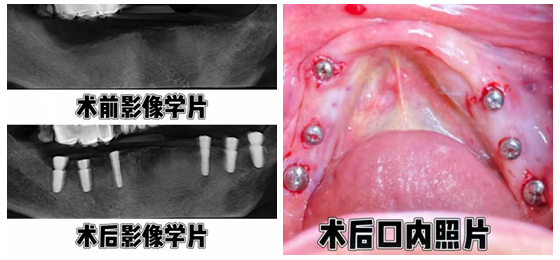

3月12日,湘雅常德医院口腔科向峰副主任医师成功为一名86岁合并高血压的高龄患者完...